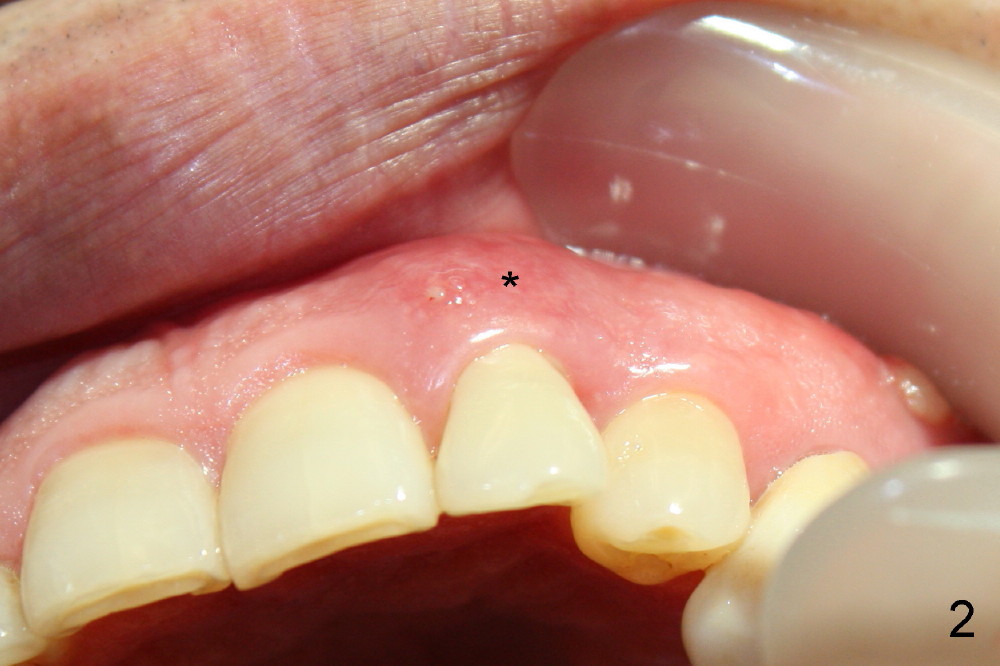

3. Gingival retraction cord #2, can be overlapped, stop bleeding, push gingiva away from prep, and most important prevent Titanium shaving from being trapped in socket

4. Rinse off metal shaving with normal saline or other before cord removal, bone graft or cementation of the provisional